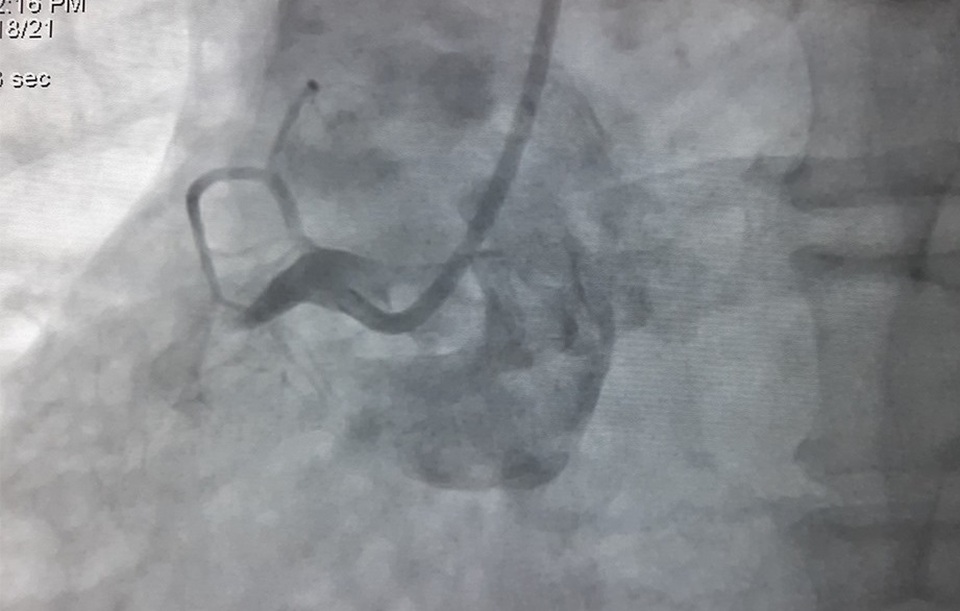

“Bệnh nhân vào viện vì đau ngực nhiều, nhịp tim chậm, huyết áp thấp. Chúng tôi tiến hành đo điện tâm đồ và phát hiện bệnh nhân bị nhồi máu cơ tim cấp nên đã hội chẩn khẩn và lập tức chuyển người bệnh vào phòng DSA chụp mạch vành cấp cứu”, bác sĩ Lạc nói.

Kết quả cho thấy, bệnh nhân bị tắc hoàn toàn động mạch vành bên phải. Các bác sĩ đã can thiệp nội mạch, đặt 1 stent tái lưu thông mạch máu cho bệnh nhân. Sau 30 phút khẩn trương, ê kíp đã đặt thành công sten tại vị trí bị tắc ở động mạch vành phải. Ngay sau khi can thiệp, bệnh nhân dần ổn định, hết đau ngực, nhịp tim huyết áp về bình thường.